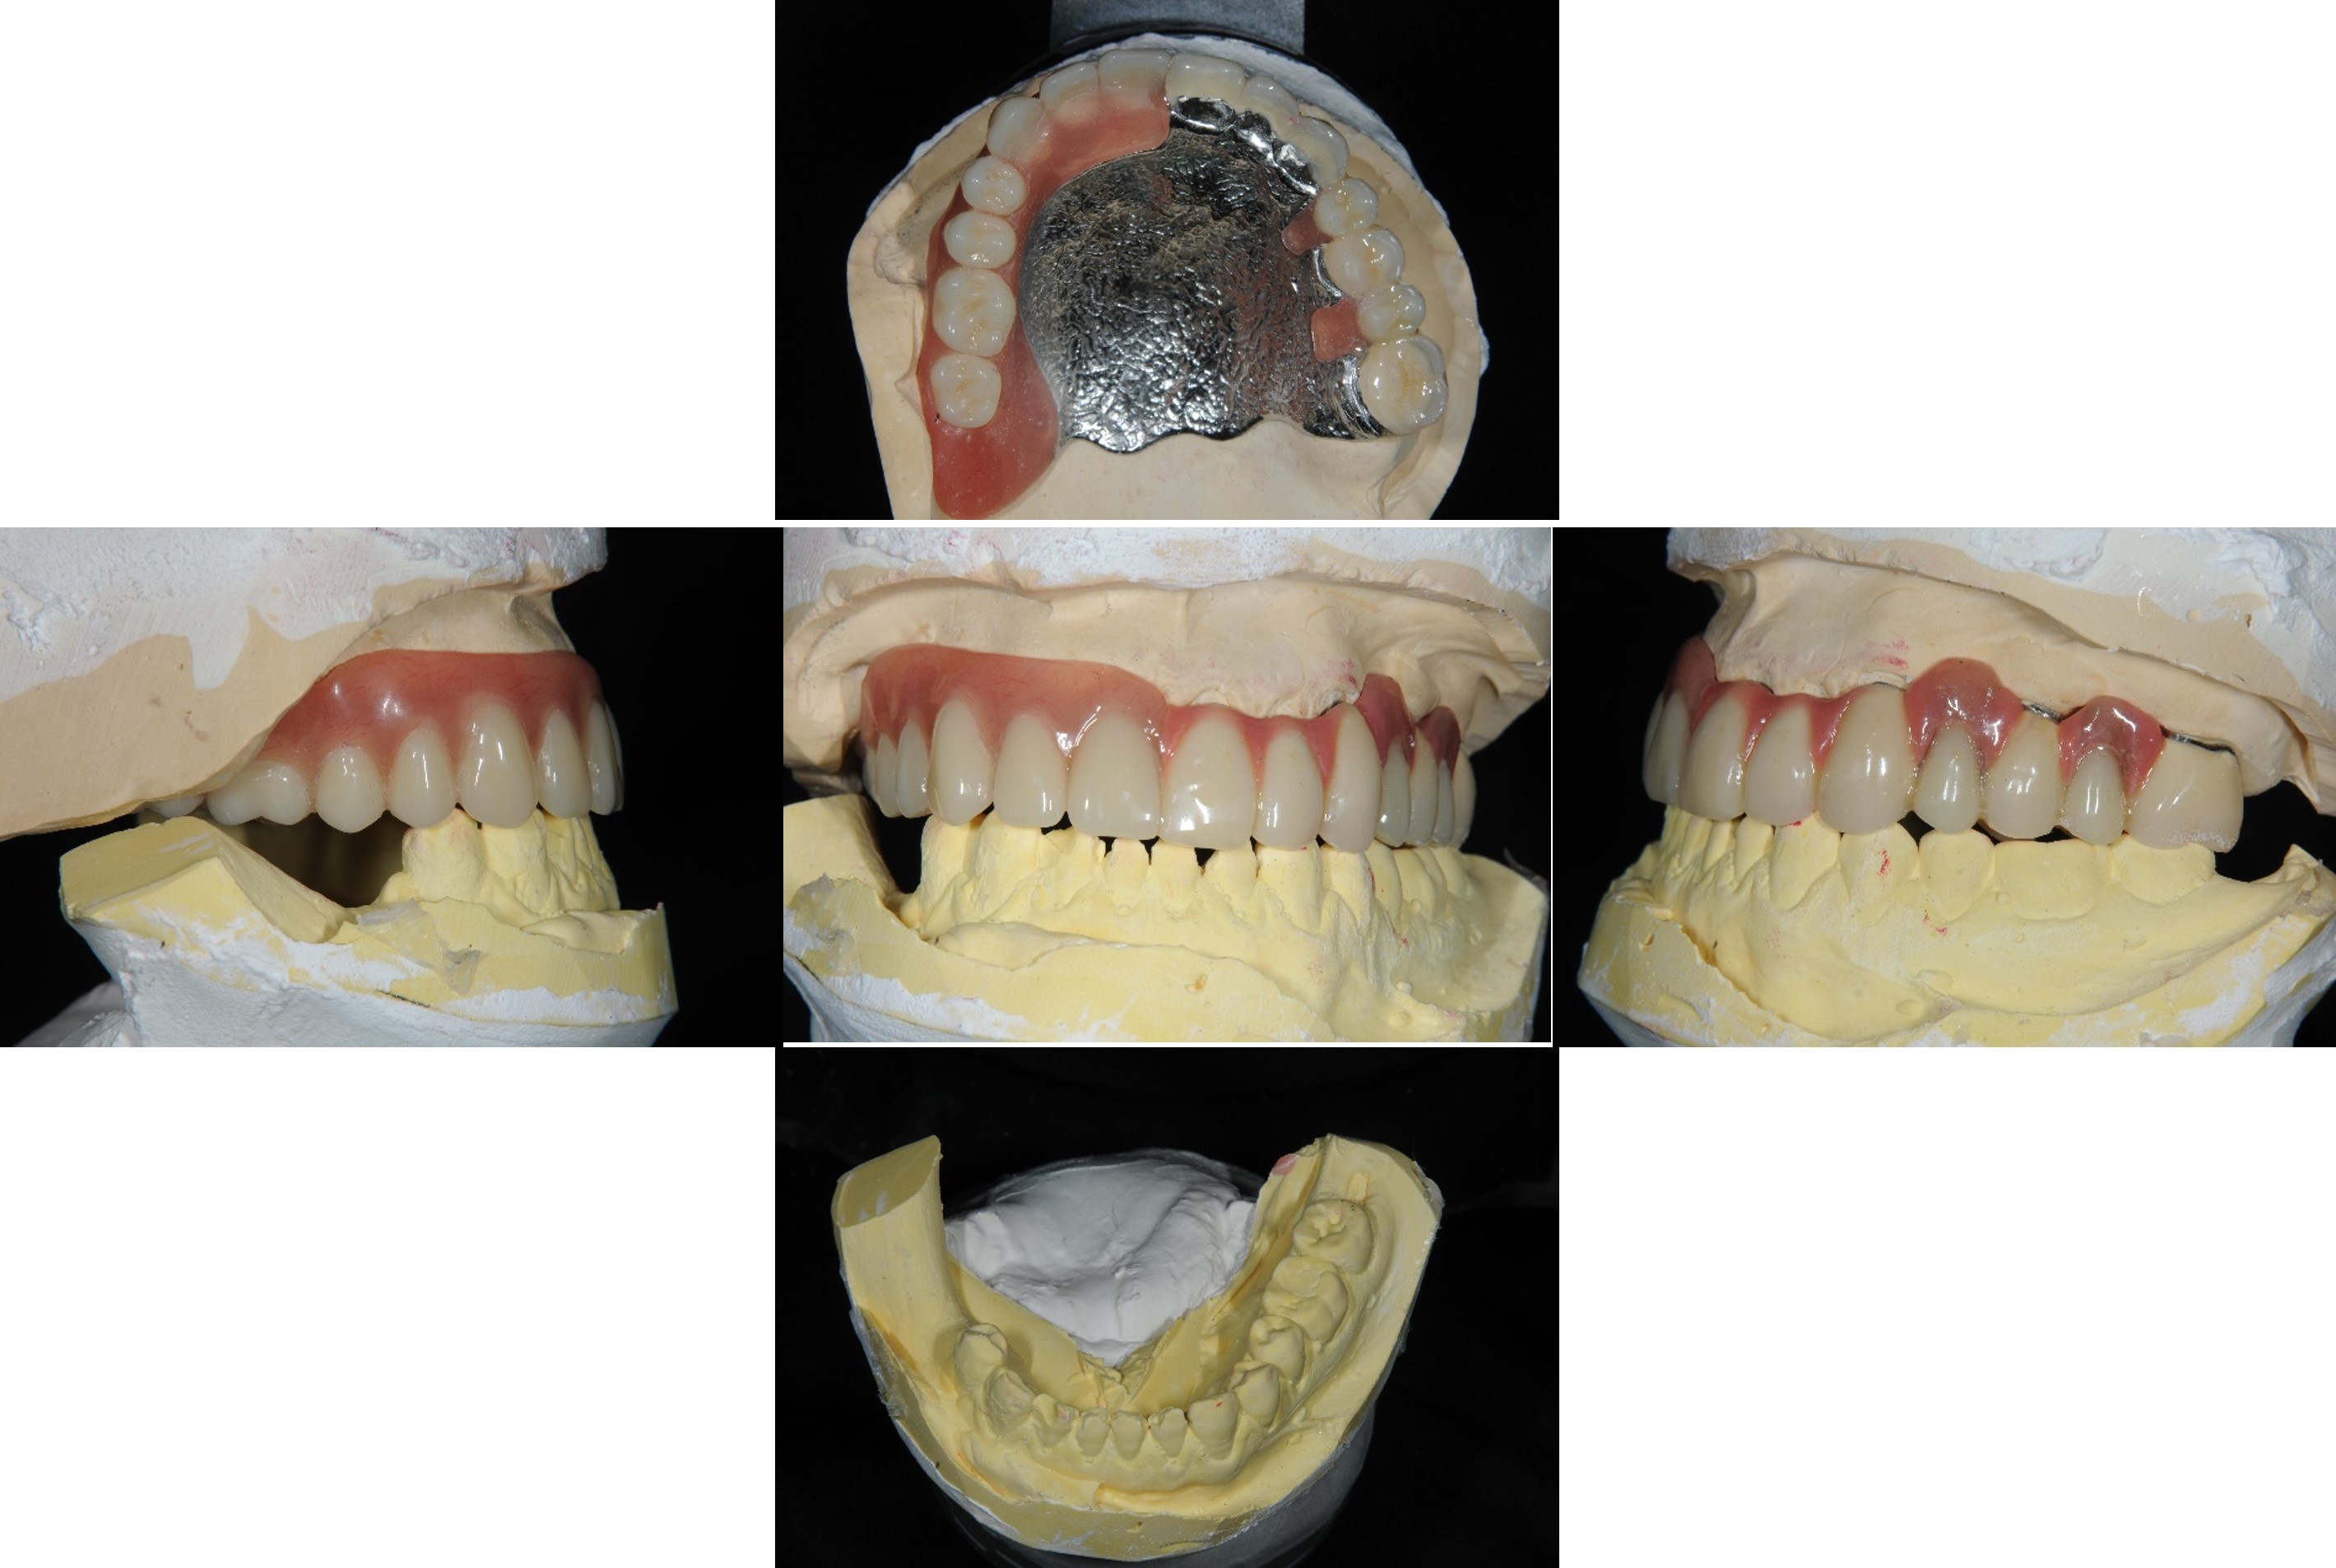

蠟型模擬最終可能成果

蠟牙製作

組合後外冠及活假牙套件

外冠及活動假牙套件

活動假牙套件